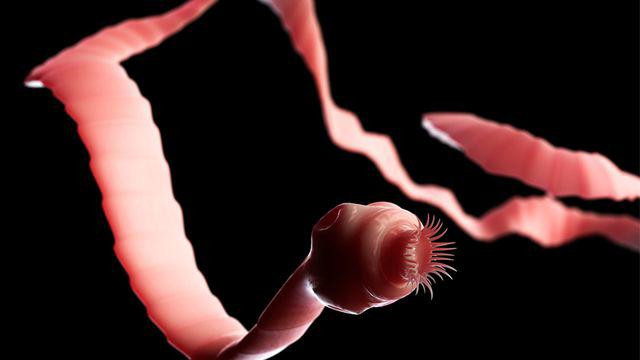

Sán dây lợn?

Sán lợn hay còn gọi là sán dây lợn có tên khoa học là Taenia solium là con sán hình dẹp có một đầu có các miệng xúc tu để bám vào thành ruột và thân là các đốt sán liên tục dính vào nhau thành một dây.

Hình ảnh sán dây lợn